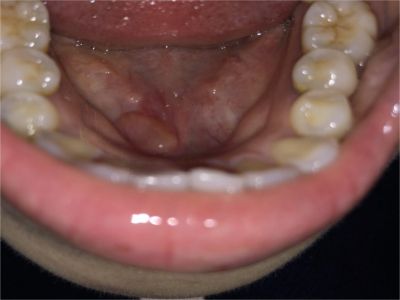

舌下腺囊肿舌头下面右侧有一个紫色包块图

舌下腺囊肿出现在口底舌系带一侧,表现为紫蓝色的隆起性包块,形态大致呈球形,界限清楚,质地柔软,囊肿增大后因破裂流出黏液。